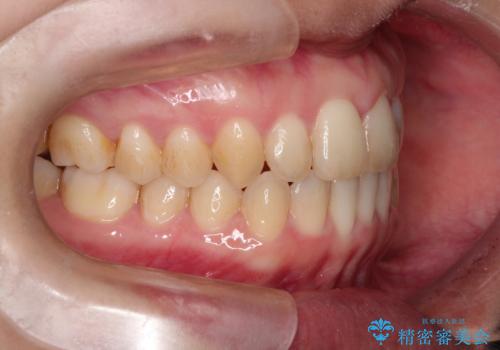

本症例は、見た目、嚙み合わせ及び、治療期間や施術内容にご満足いただきました。